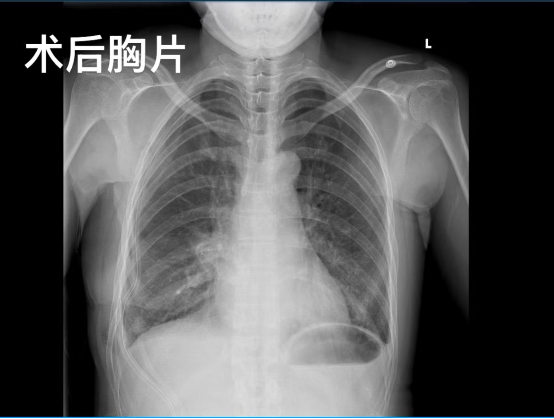

經(jīng)與李女士進(jìn)行充分的術(shù)前溝通,5月9日,手術(shù)進(jìn)行。在麻醉手術(shù)中心團(tuán)隊(duì)和護(hù)理團(tuán)隊(duì)的配合支持下,胸外科團(tuán)隊(duì)和乳腺疾病中心團(tuán)隊(duì)在乳暈外側(cè)邊緣開一個(gè)小切口,通過腔鏡技術(shù),在3個(gè)多小時(shí)內(nèi),一氣呵成完成了“右乳癌保乳”“右乳前哨淋巴結(jié)活檢”“右肺中葉切除”“葉特異性淋巴結(jié)清掃”手術(shù)操作。術(shù)后,李女士恢復(fù)較好,3天后順利出院,住院時(shí)長與普通肺癌患者相同。一個(gè)月后復(fù)查,李女士僅乳暈處有一個(gè)長約8厘米的傷口,傷口恢復(fù)良好,乳腺、肺部檢查均正常;8月底再次復(fù)查,李女士復(fù)查結(jié)果正常。